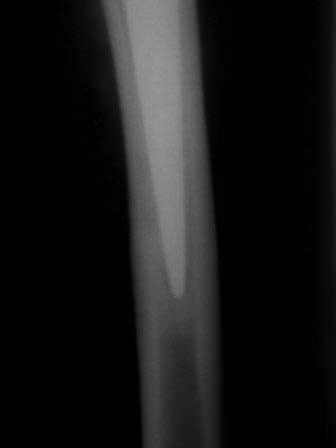

Уважаемые коллеги. Обратилась наша коллега, 1964 г.р. В 2008 году перенесла тяжелый анафилактический шок (гемодез), получила большие дозы гормонов, через 6 месяцев развился асептический некроз головок обеих бедренных костей.

В апреле и июле 2009 года было произведено эндопротезирование обеих т/б суставов в ТашМИ., с тех пор беспокоият боли в правой ноге, особенно сильно стартовые боли - первые шаги, потом боль уменьшается, но не исчезает, сильно хромает, долго ходить не может, постоянно употребляет НПВС. В последнее время боли усиливаются, боли в основном в паховой области и медиальнее в глубине, а также на уровне с/з диафиза бедра. Левая нога не беспокоит. Очень просит помощи. Уважаемые коллеги, как можно ей помочь? В крайним случае согласна и на реимплантацию! Или может быть есть более щадящие и недорогие методы.